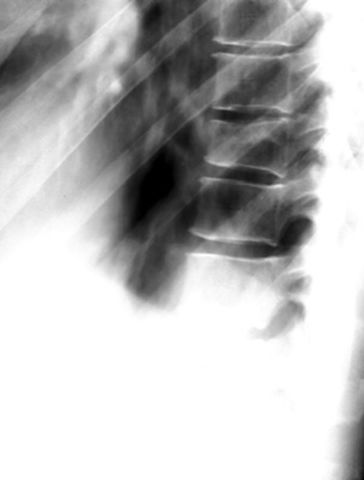

L5腰椎骨折